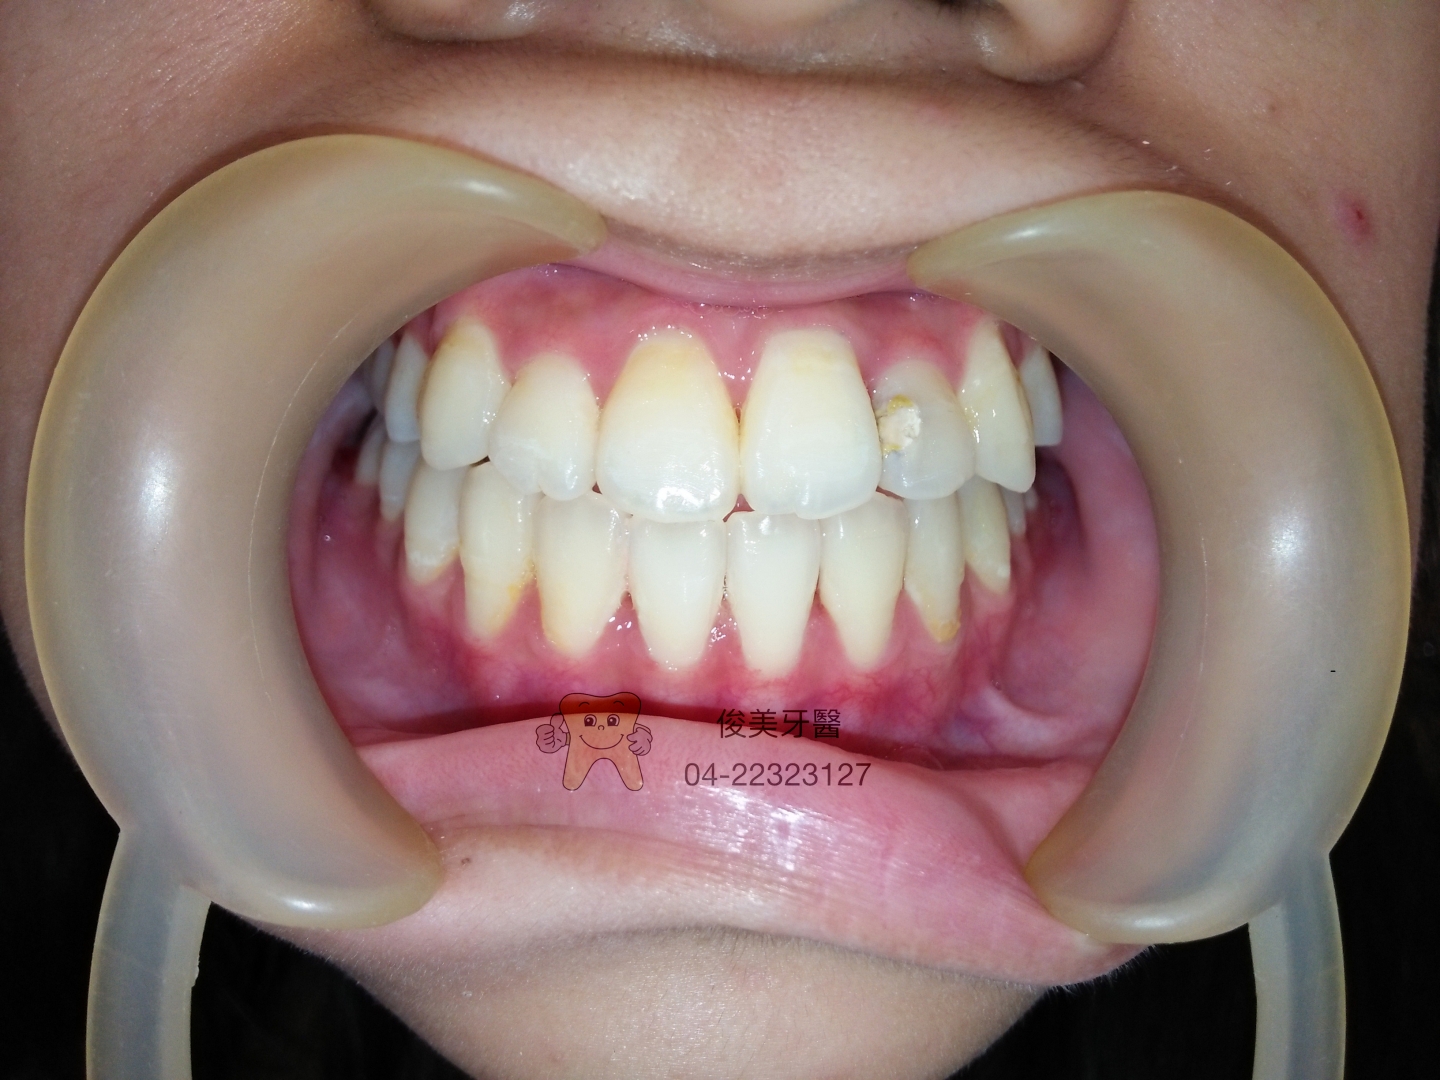

經過一年半的治療,結果讓家長滿意,不但牙齒排整齊了,好清潔,也好咀嚼食物,

不再阻礙孩子展露充滿自信的笑容。

牙齦紅腫的現象也明顯改善不少。

目前配戴維持器,定期回診即可。